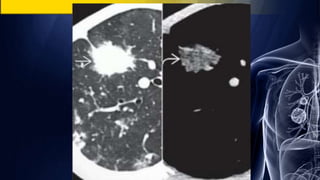

Air bronchogram

Air bronchogram on CT

Bronchoalevoler

carcinoma

Pulmonary lymphoma Round Pneumonia

Air bronchogram Air bronchogramon CT Bronchoalevoler carcinoma Pulmonary lymphoma Round Pneumonia